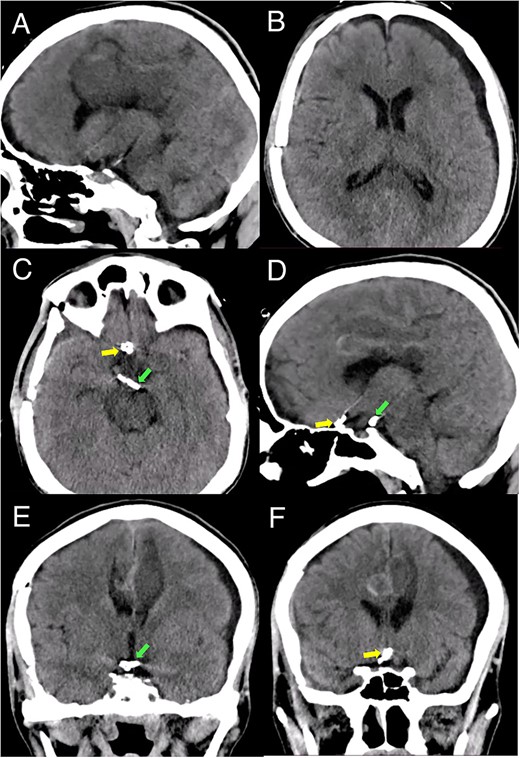

Brain imaging demonstrated improvement of the hematoma and intraventricular hemorrhage with remnant postinfarction areas (Fig. 4). The patient was transferred to neurointensive care postoperatively, where he remained for 7 days. At this point, the neurological examination indicated he had 4/5 quadriparesis, a right third nerve paresis, and a GCS score of 13. Seven days later, he was discharged with a modified Rankin scale (mRS) score of 4. At the 1-month follow-up, the patient had a GCS of 14 and a mRS of 4. At the 3-month follow-up, the patient showed a significant improvement in the GCS score with a mRS of 2 and improved function of the right third cranial nerve.

Postoperative head CT. (A, B) Sagittal and axial views show resolution of the hematoma and intraventricular hemorrhage with remaining postinfarction areas. (C–F) Postoperative head CT views depict the placement of clips in the accessory A2 artery (yellow arrow) and basilar aneurysm (green arrow).